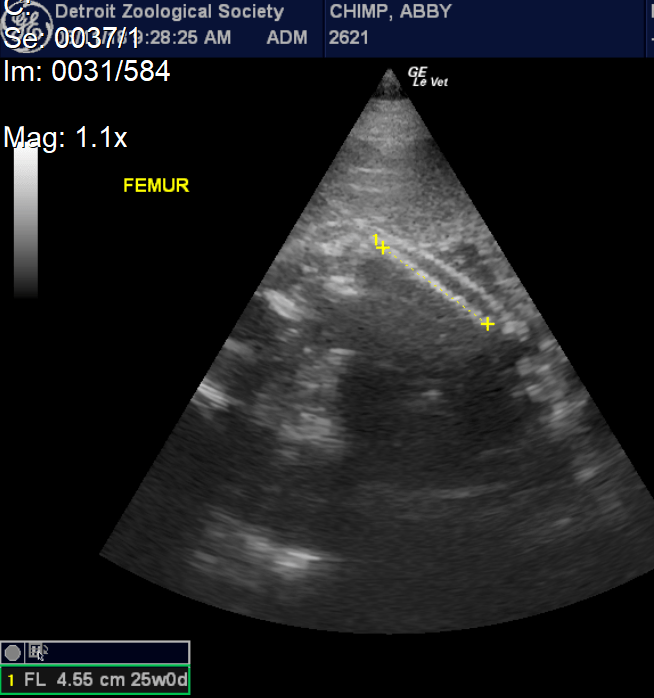

Abby was a cooperative patient and always appeared excited to see us. She would prop herself on a ledge and eat peanuts during each exam, allowing the peanut shells to pile up on her growing belly. There are limits to the ways we can position the probe, and we were not always able to get every measurement at every visit. In the early months, we were able to measure the length of the fetus from the crown to the rump; as the baby grew, we measured the circumference of the head and abdomen and length of the long bones, including the femur and humerus. We were also able to see the position of the fetus and measure the heart rate. With each exam, we added data to our growth charts, and were pleased to see steady growth and development. We also became increasingly confident that the baby was a girl.

Abby is the third chimpanzee mom that has allowed us to conduct obstetrical ultrasounds, and since 2008 we have been able to collect measurements from three pregnancies, including youngsters Ajua and Akira. Using these measurements and data from two scientific publications, we were able to make a solid prediction of Abby’s due date – July 14, the date of the first annual World Chimpanzee Day! As this date approached, animal care staff began round-the-clock checks to look for signs of labor. Just three days before the due date, we performed a final ultrasound exam. We were pleased to see that the baby was still growing according to expectations. We could see her face and watch her open and close her mouth and wiggle her arms and legs. Most importantly, we could see that the baby had a strong heartbeat and was positioned with her head down, which is the correct position for a normal delivery.